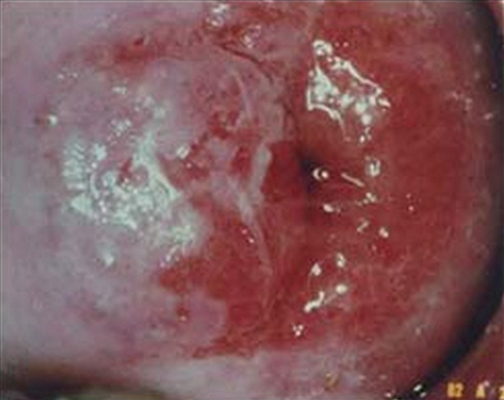

淋病圖片

淋病的症狀 (7)

淋病的症狀 (8)

淋病的症狀 (9)

淋病的症狀 (47)

淋病的症狀 (48)

淋病的症狀 (49)

淋病的症狀 (5)

淋病的症狀 (50)

淋病的症狀 (51)

淋病的症狀 (52)

淋病的症狀 (53)

淋病的症狀 (54)

淋病的症狀 (55)

淋病的症狀 (56)

淋病的症狀 (6)

淋病的症狀 (40)

淋病的症狀 (41)

淋病的症狀 (42)

淋病的症狀 (43)

淋病的症狀 (44)